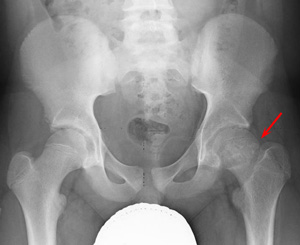

X-ray of a 12-year-old boy with stable SCFE in his left hip (arrow).

Reproduced from Weber MD, Naujoks R, Smith BG: Slipped capital femoral epiphysis. Orthopaedic Knowledge Online Journal 2008; 6(2). Accessed June 2016.